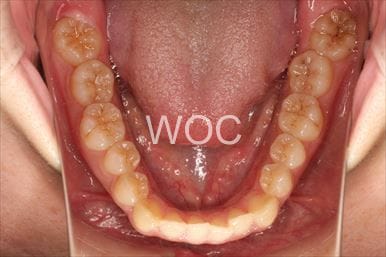

治療前1

治療前2

治療前3

治療前4

治療前5

- 年齢:20歳女性

- 主訴:出っ歯が気になる

- 基本矯正料金:120万円

- 治療期間:1年7ヶ月

- 抜歯部位:上顎両側第一小臼歯